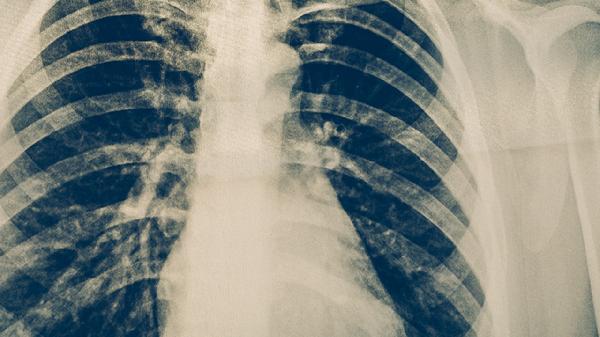

每周監(jiān)測血糖譜,每月檢測糖化血紅蛋白。每2個月復查胸部CT評估結(jié)核病灶變化。關注周圍神經(jīng)病變、視網(wǎng)膜病變等糖尿病并發(fā)癥。若出現(xiàn)咯血、持續(xù)發(fā)熱或呼吸困難需立即就醫(yī)。